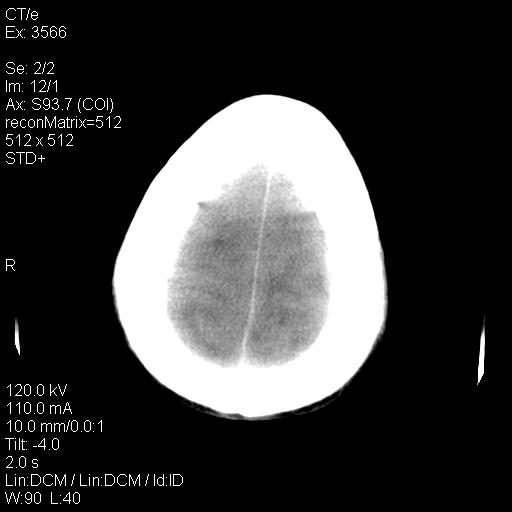

标题: CT9947:女,20岁,妊娠9个月,突然癫痫症状 [打印本页]

标题: CT9947:女,20岁,妊娠9个月,突然癫痫症状

双侧脑白质缺血缺氧性改变,并高度可疑“蛛网膜下腔出血”。

后可复性脑病,

考虑 妊娠子痫或妊高征

双侧脑白质缺血缺氧性改变.

考虑先兆子痫\\子痫致he,建议mri除外有无合并静脉窦血栓形成.

考虑pres

的确应该考虑可逆性后部脑病综合症--pres。感谢天南地北老师的指引,又学了一招儿,开心,呵呵!

考虑可逆性后部脑病综合症

支持pres